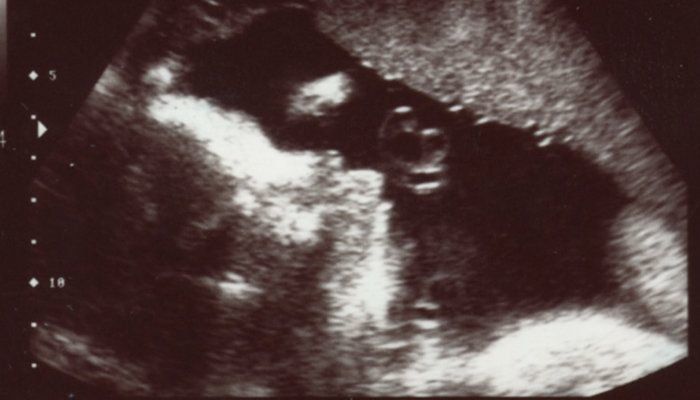

チャーミー小結さんの妊娠30週目のエコー写真

口をキュッとつぐむ様子も愛おしい表情。この頃は便秘がひどく、「酸化マグネシウム」を医師に処方してもらいました。この頃は安静にしながらも、週に1回催される母親学級へ車椅子で通い勉強していました。